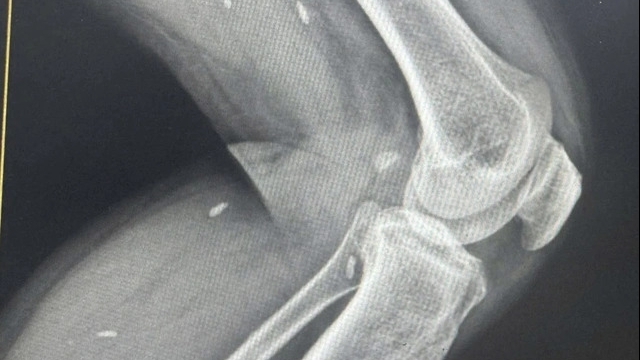

Sau 5 ngày điều trị, bệnh nhân đã được giải các độc chất và thoát cơn nguy kịch, giữ được tính mạng. Tuy nhiên bệnh nhân vẫn còn những di chứng đối với thần kinh (chụp cộng hưởng từ có tổn thương trên não) và thị giác (hiện tại vẫn nhìn mờ cả hai mắt) nên sẽ được chuyển đến Khoa Mắt để tiếp tục điều trị.